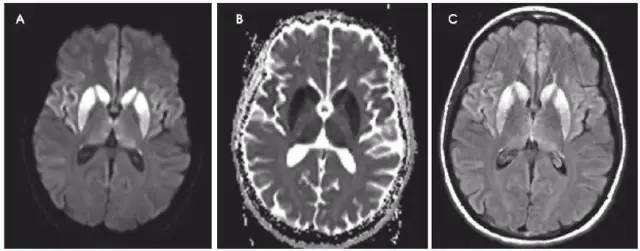

缺血缺氧性脑病(HIE)是全脑缺氧的结果。最常见的原因是心脏骤停、呼吸衰竭和休克。严重的患者大脑皮质和深部灰质均受累(图1)。

较轻的患者可以见到边缘带梗死类型。罕有纯白质型,这可能是全脑缺血诱发脱髓鞘表现。小脑通常不受累。

图1 一例31岁男性,有海洛因和可卡因滥用史,出现无脉性电活动心搏骤停。MRI显示双侧顶枕叶和额叶、双侧丘脑弥漫性弥散受限(A:DWI,B:ADC)、T2-FLAIR高信号(C:FLAIR),符合全脑缺氧性损伤。